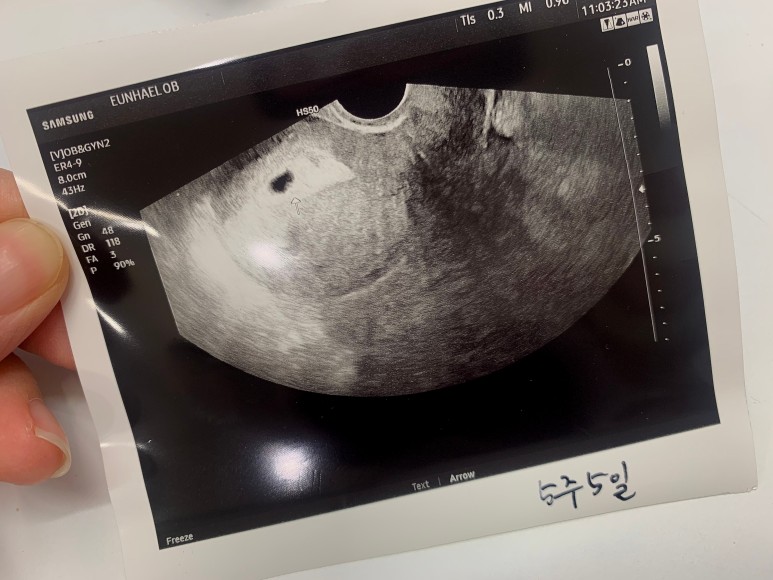

6주가 되니 작지만 동그란 아기집이 보였다. 자세히 보면 동그란 아기집 안에 난황도 보였다.

선명한 아기집을 두 눈으로 확인하고 나니 10% 정도 실감이 났다.